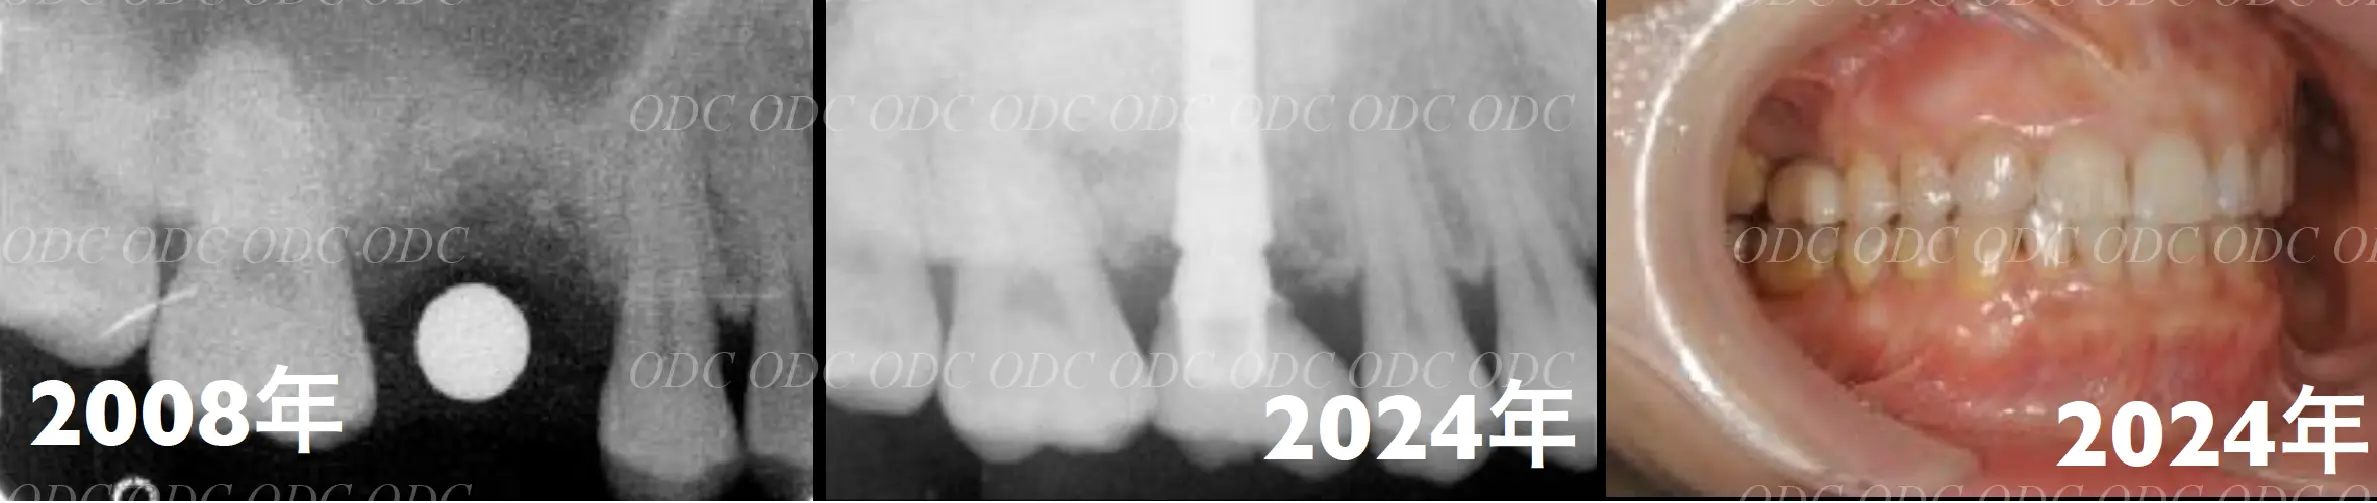

2008年、第一大臼歯の歯根破折を主訴に来院された。

サイナスリフト後にインプラント埋入。

左は術前のレントゲン写真。中央、右は2024年、術後約16年後のレントゲン写真と口腔内写真。

1枚目上、奥歯2本欠損でインプラント治療を希望された。サイナスリフト後、インプラント埋入。

2枚目、術後約10年経過。レントゲン的にも経過良好です。